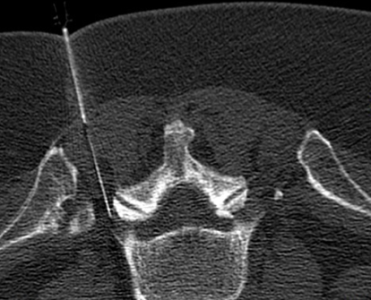

Vertebroplastie/Kyphoplastie

Durch Stabilisierung eines gebrochenen Wirbelkörpers (z.B. bei Osteoporose) mit Knochenzement kann eine rasche Beschwerdelinderung mit geringem operativen Risiko für den Patienten ermöglicht werden.